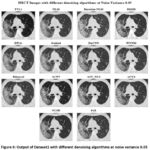

![]() |

Figure 5: Output of Dataset1 with different denoising algorithms at noise variance 0.01 |

Figure 5 presents HRCT images denoised by various algorithms at a Noise Variance (N.V.) of 0.01. The performance of each algorithm in noise reduction and structural preservation is quite different, as shown in the figure. Among these methods, BM3D shows the best performance, maintaining sharp edges and preserving fine details while effectively suppressing noise. Similarly, DnCNN, a deep-learning approach, also presents a high-quality balance between noise reduction and detail preservation. Its performance is close to that of BM3D. The image remains sharp with clear edges and minimal blurring. WNNM shows effective noise suppression but causes the loss of some texture details compared with BM3D and DnCNN. EPLL shows good denoising power but looks over-smoothed, resulting in the loss of finer anatomical structures, which may affect clinical interpretations. Guided Filtering shows visible noise reduction but also introduces some level of blurring, which is detrimental to the clarity. Though the lung structures are still separable, they are not as sharp as in BM3D or DnCNN. Similarly, Bilateral Filtering provides a moderate level of denoising but still exhibits some graininess, and edges appear less sharp compared to BM3D or WNNM. Other methods like ACPT, AST_NLS, and ACVA show reasonable noise removal capabilities. Their ability to preserve structural details varies, though. Among these, ACVA seems to provide the best perceptual quality. NLM and Bayesian NLM are known to work fairly well for low noise variance but result in low-level blurring while reducing noise. On the other hand, FoE produces a noisier result, which is not sharp and cannot suppress noise well, and the image looks less clear than those processed with BM3D or DnCNN. NCSR provides moderate performance but with some blurring and loss of texture details. Finally, TVL1 is the worst-performing algorithm in this set, causing severe loss of structural information. The result seems over-smoothed with misaligned details, and so it cannot be used in medical applications.

Figure 6: Output of Dataset1 with different denoising algorithms at noise variance 0.05 |

Figure 6 shows the denoised HRCT images using a variety of algorithms at a Noise Variance (N.V.) of 0.05. Among the methods, BM3D remains one of the best-performing techniques, effectively suppressing noise while maintaining fine anatomical structures with clear contrast. DnCNN also demonstrates strong performance, preserving sharp edges and lung structures while reducing noise, making it a reliable deep-learning-based denoising approach. WNNM continues to have the denoising capability without significant noise reduction but the loss in the fine details. Guided Filtering and EPLL significantly remove the noise, but the amount of over-smoothing diminishes the visibility of the small lung structures. Bilateral Filtering gives medium denoising performance but continues to exhibit a lot of noise artifacts with the blurring of fine details. ACPT, AST_NLS, and ACVA balance noise removal with structural preservation, with ACVA producing relatively clearer results. However, Bayesian NLM and NLM (Non-Local Means) suffer at the cost of noise variance with increased graininess, but a lesser sharpness level. Noisiness is more prevalent with FoE and NCSR than with other techniques since they cannot successfully remove the noise while retaining structural integrity. The worst one was TVL1 (Total Variation L1 Norm), highly over-smoothing and anatomically distorted. As the noise variance increases to 0.05, BM3D and DnCNN continue to demonstrate the best balance between noise suppression and structural preservation, making them the most effective choices for medical imaging. WNNM and ACVA offer moderate results but still introduce some loss of fine details. In contrast, TVL1, FoE, and Bayesian NLM struggle to produce clinically viable outputs due to excessive blurring or retained noise artifacts. At higher values of noise, deep learning types such as DnCNN and advanced filtering types like BM3D are more preferred in medical imaging, where anatomical structures have to be preserved for precise diagnosis.